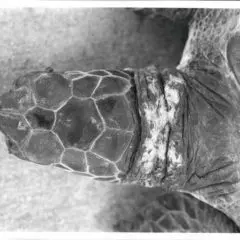

2024- Four Decades of Green Turtle Strandings on Hawai‘i Island (1983–2022): Causes, Trends, and Future Mitigation. By Skylar Dentlinger et al. HCC Poster.

2024- Published: UH Hilo alumna investigates four decades of green sea turtle strandings on Hawaiʻi Island.